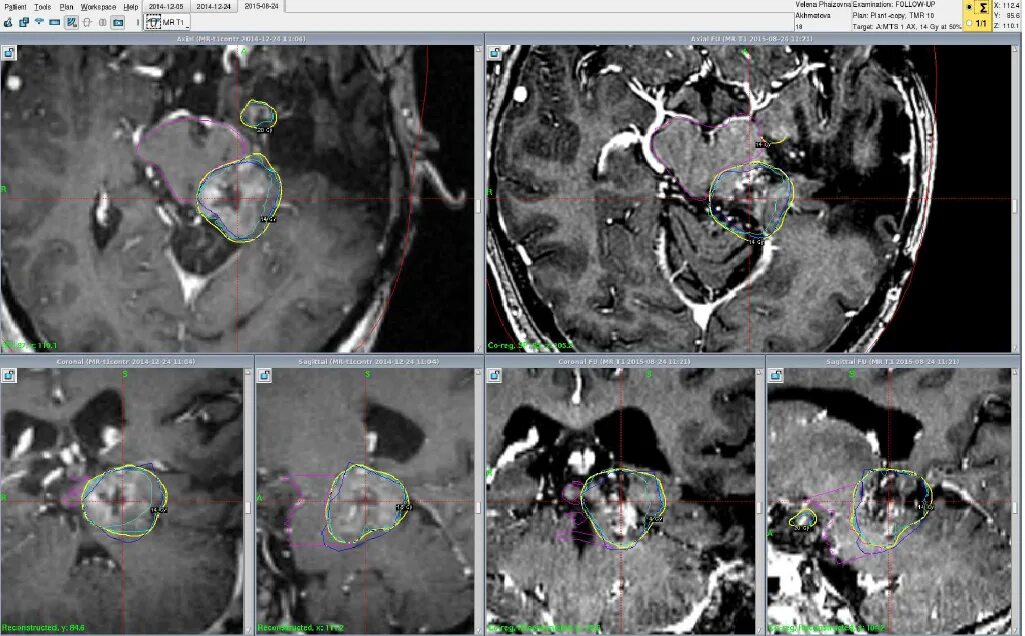

Вероятность метастаз